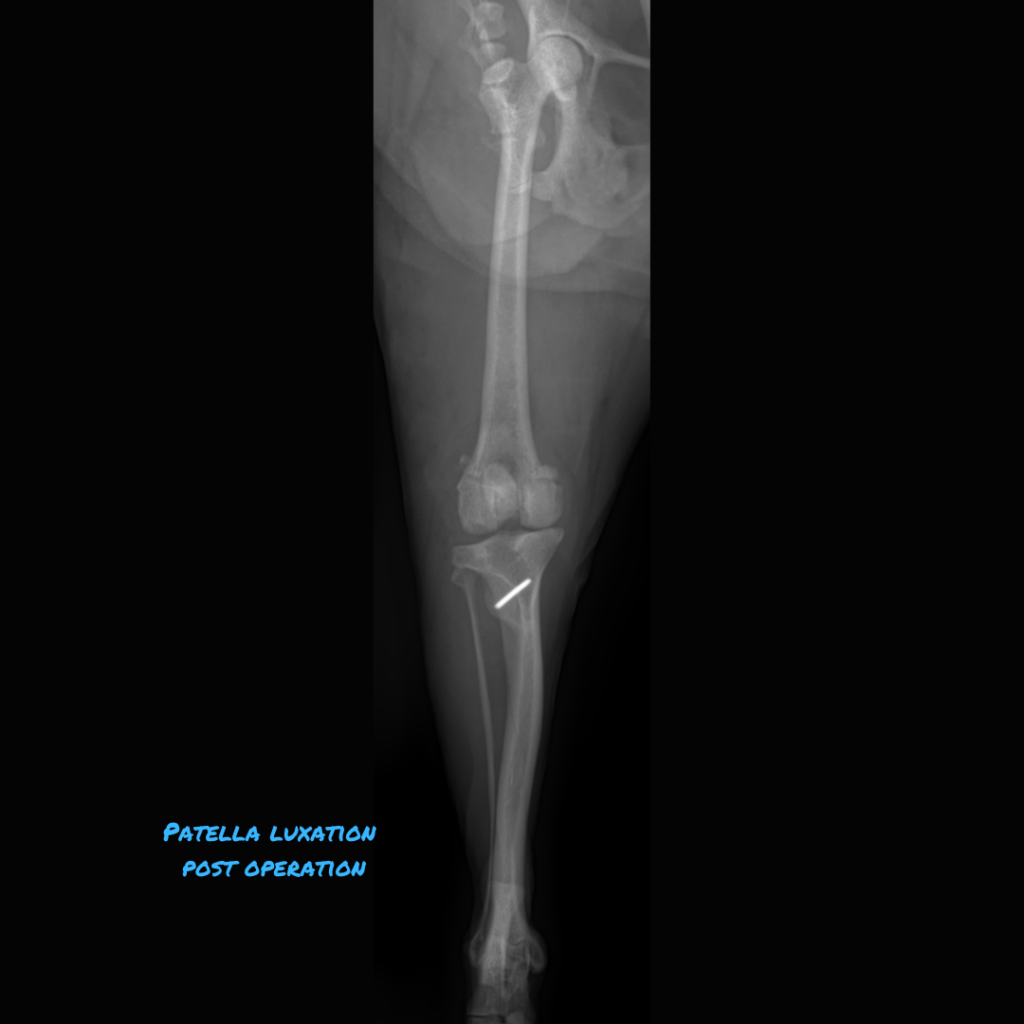

[Pic 2: The tibial tuberosity was shifted laterally and the groove was made deeper, so the patella is now sitting in its proper spot in the middle. (blue dotted line)